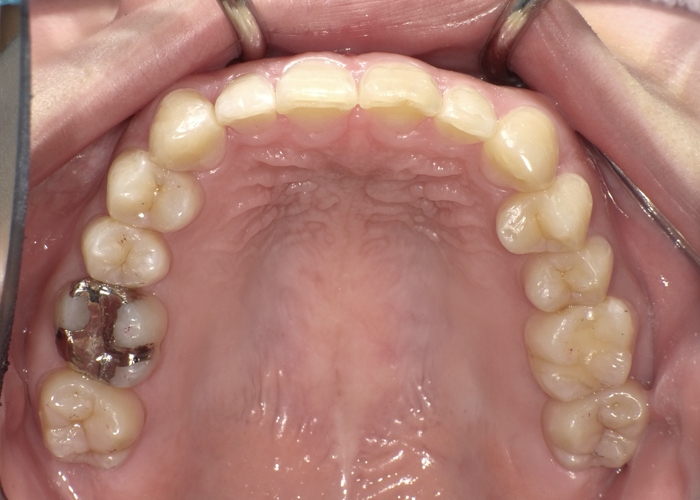

初診時の口腔内写真

術前の口腔内写真

上の前歯(左上1)は外側に、下の前歯(左下1)は内側にあります。

歯ブラシが難しいため、着色や虫歯・歯周病のリスクが高い状態です。